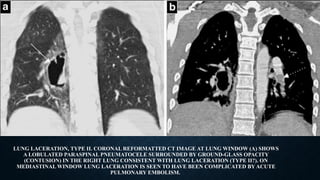

LUNG LACERATION, TYPE II. CORONAL REFORMATTED CT IMAGE AT LUNG WINDOW (A) SHOWS

A LOBULATED PARASPINAL PNEUMATOCELE SURROUNDED BY GROUND-GLASS OPACITY

(CONTUSION) IN THE RIGHT LUNG CONSISTENT WITH LUNG LACERATION (TYPE II?). ON

MEDIASTINAL WINDOW LUNG LACERATION IS SEEN TO HAVE BEEN COMPLICATED BY ACUTE

PULMONARY EMBOLISM.

LUNG LACERATION, TYPEII. CORONAL REFORMATTED CT IMAGE AT LUNG WINDOW (A) SHOWS A LOBULATED PARASPINAL PNEUMATOCELE SURROUNDED BY GROUND-GLASS OPACITY (CONTUSION) IN THE RIGHT LUNG CONSISTENT WITH LUNG LACERATION (TYPE II?). ON MEDIASTINAL WINDOW LUNG LACERATION IS SEEN TO HAVE BEEN COMPLICATED BY ACUTE PULMONARY EMBOLISM.